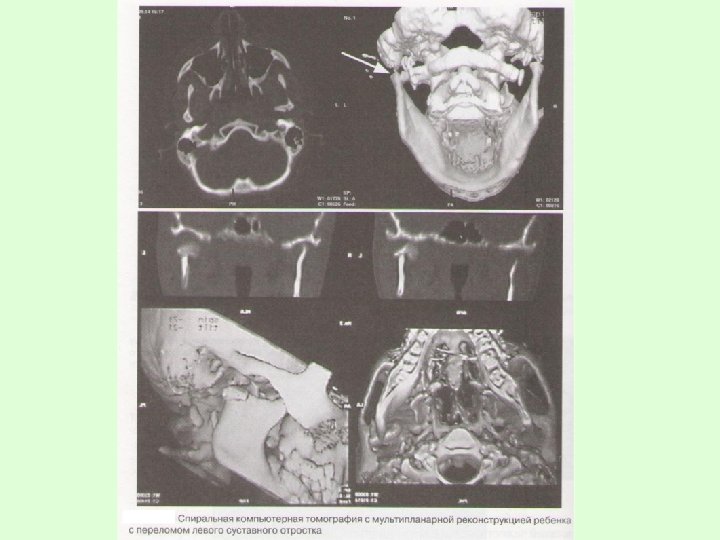

На рентгенограммах обычно определяется нарушение целостности костной ткани, наличие линии перелома, смещение отломков челюсти. В сложных диагностических случаях переломов суставного отростка нижней челюсти у детей для постановки окончательного диагноза при отсутствии явных клинических и рентгенологических признаков используют метод спиральной компьютерной томографии с мультипланарной реконструкцией.